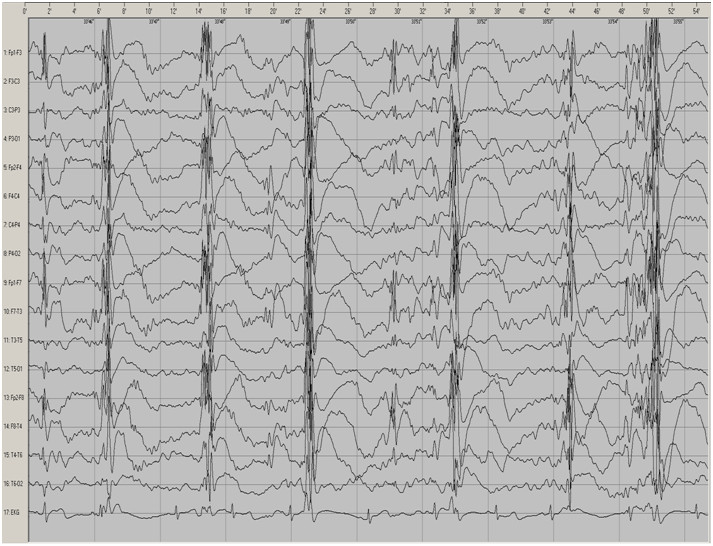

Poniższy śródnapadowy zapis czynności bioelektrycznej mózgu wykonano u 12-letniego pacjenta. W czasie tego badania zarejestrowano następujący typ napadów padaczkowych: